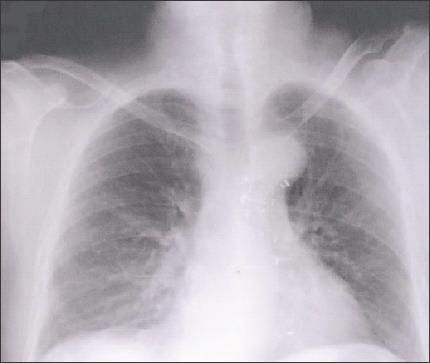

Bilirubin level was elevated at 2.2 mg/dL, alkaline phosphatase level was 309 U/L, aspartate aminotransferase (AST) level was 561 U/L, and alanine aminotransferase level was 288 U/L. Achest radiograph demonstrated perihilar interstitial infiltrates predominantly in the right middle and lower lung fields (Figure).

Perihilarinterstitialinfiltrates arepredominantlyseen in the rightmiddle and lowerlung fields in thischest radiograph.